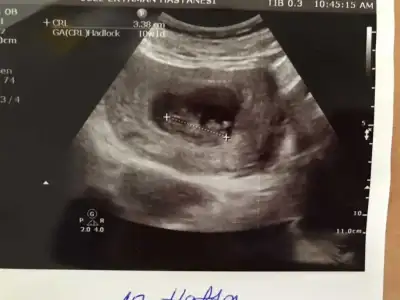

@Ikra meyra banada tahminde bulunurmusun canım ilk fotoğraf 9 haftalık ikincisi 13+5 Ikra meyra Ikra meyra 🥰

• image.webp

image.webp

18,8 KB · Görüntüleme: 82